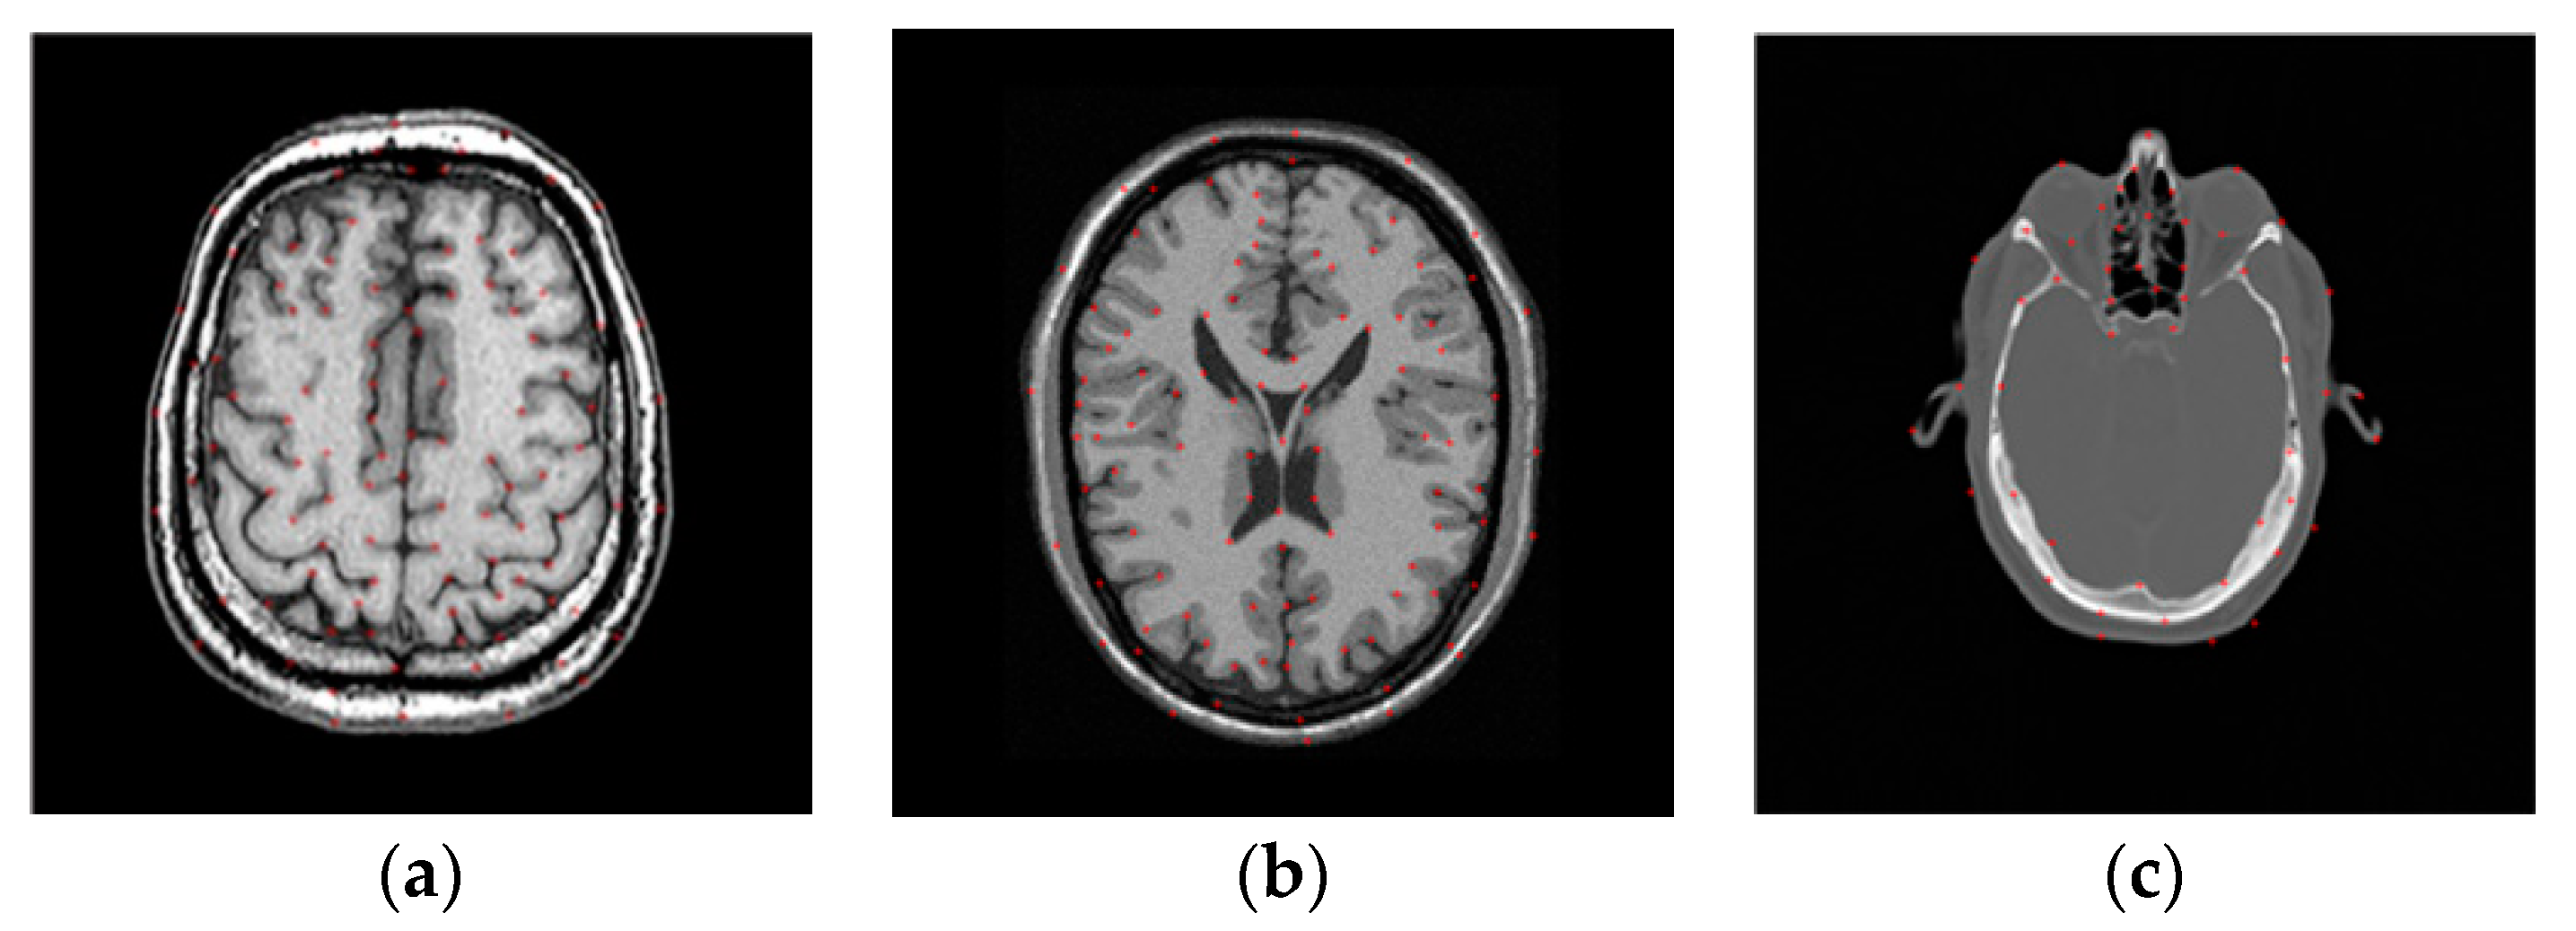

3.2.2. Test on the RIRE Dataset